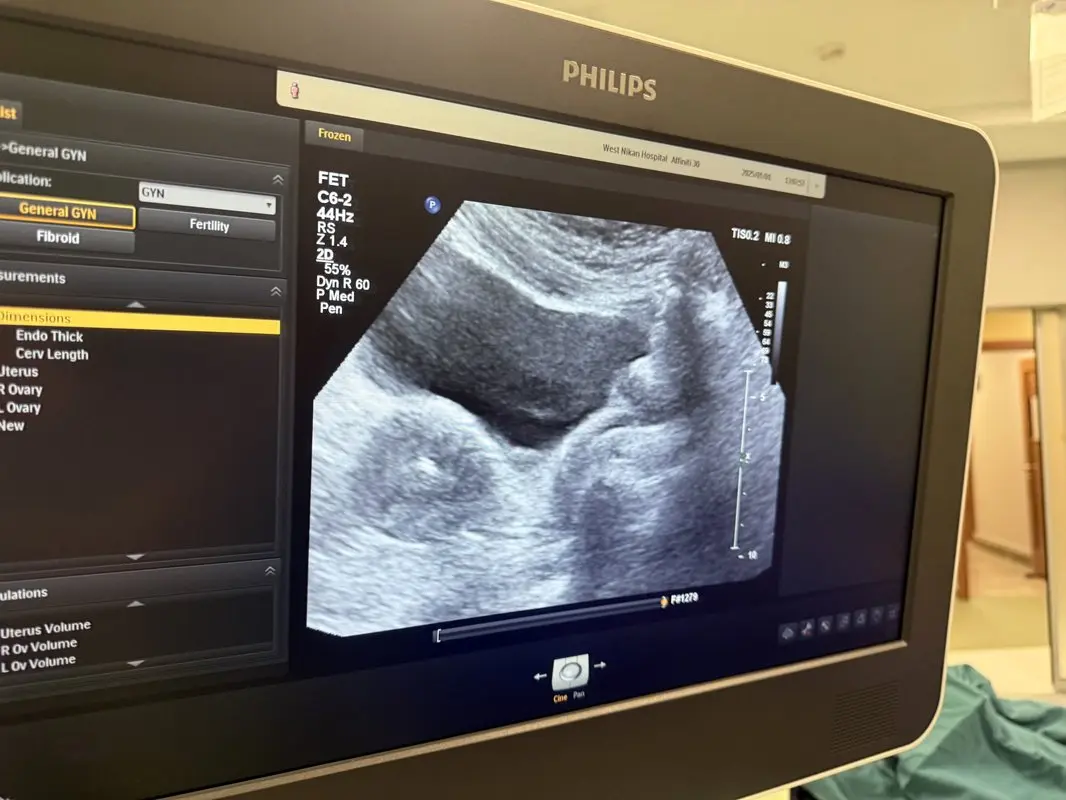

دکتر پریسا طاهرزاده این عکس را به اشتراک گذاشت و در توضیح آن نوشت: اولین انتقال جنین سال ۲۰۲۵ ، رویان ۴ روزه که امروز انتقال دادم و امیدوارم باردار بشه